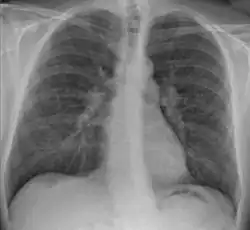

![]() | |

| Chest X-ray showing the typical nodularity of sarcoidosis, predominantly in the hila of the lungs. | |

-

Hilar adenopathy especially on the person's left (AP CXR) -